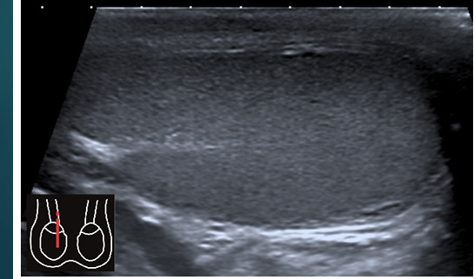

what do you see

what do this images show

Epididymal cyst- US